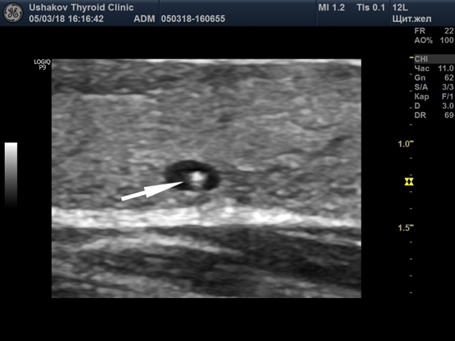

Кистозные образования щитовидной железы при УЗИ

Обычно выявляются аваскулярные (74%) округлые (62%) или овоидные (34%) анэхогенные (100%) образования с ровными четкими контурами (97%) с дистальным псевдоусилением эхосигнала (76%) и боковыми акустическими тенями.

Во внутренней структуре кист часто выявляются гиперэхогенные артефакты по типу «хвоста кометы», который образуется в результате отражений и преломлений ультразвуковых волн при их прохождении через густую коллоидную жидкость.

Эхографически «хвост кометы» визуализируется как яркий гиперэхогенный эхосигнал, имеющий вид «перевернутой капли».